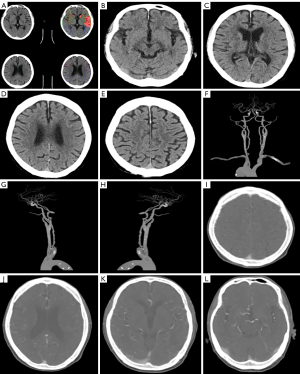

Laboratory tests revealed a white blood cell count of 14.3×109/L, of which, eosinophils accounted for 47.4% (absolute value: 6.76×109/L), and a platelet count of 64×109/L. An emergency triple head computed tomography (CT) [plain scan + computed tomography angiography (CTA) + computed tomography perfusion (CTP)] ruled out hemorrhage and major vascular lesions (Figures 1,2). Upon admission, the patient reported a 15-hour history of symptoms, exceeding the standard 4.5-hour time window for intravenous thrombolysis (IVT) as per the American Heart Association/American Stroke Association guidelines (13). Additionally, the laboratory results revealed a platelet count of 64×109/L, which further contraindicated IVT due to an increased risk of bleeding. Head CTA and CTP excluded large-vessel occlusion, and thrombocytopenia necessitated cautious anticoagulation strategies over thrombolytic therapy.

The patient’s response to corticosteroids and durable remission further supported a diagnosis of idiopathic HES (28). Notably, while emergency triple head CT (plain scan + CTA + CTP) revealed no large-vessel occlusion or perfusion abnormalities, subsequent MRI confirmed an acute infarction in the basal ganglia, showing that eosinophil-mediated microvascular embolism may evade detection on routine imaging (29). The imaging-clinical discrepancy suggests a unique “biphasic pattern” in eosinophil-related cerebral infarction, characterized by direct blood-brain barrier disruption via eosinophil granule proteins and microcirculatory disturbances from the release of procoagulant substances like tissue factor and plasminogen activator inhibitor-1 (30). This observation provides two key clinical insights: (I) negative CTA results do not exclude idiopathic HES-related cerebral infarction, requiring close monitoring for distal microvascular embolism induced by eosinophil microparticles; and (II) eosinophil-derived extracellular traps, forming a “thromboinflammatory network” via NETosis can sustain thrombosis even with normal vascular imaging (31).